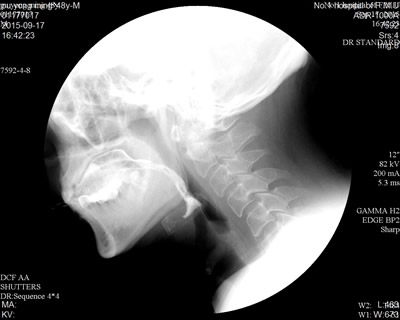

病例:患者,男性,48岁,以“突发右侧肢体无力1月余”为主诉入院。结合影像学表现,诊断为:脑干出血恢复期。患者临床表现为右侧肢体瘫痪伴面瘫。患者在食用稀流质时,常出现呛咳、偶有误吸,曾多次导致肺部感染。经过康复科初期吞咽治疗后,患者呛咳症状较前稍好转。为求进一步精准治疗,康复科专家决定对患者行“吞咽造影录像检查与评估”。在造影下可见:患者在食用对比剂后,单次吞咽,部分食物残留在口腔、会厌谷及梨状窝内(图a、b),经过反复吞咽后可把全部食物送入食管,未见明显呛咳。经过评估,患者的呛咳主要是由于面肌的瘫痪,食物无法有序、可控的输送至咽部所致,经过加强患者面肌收缩动作的训练以及指导患者在进食时进行点头吞咽、交互吞咽,现患者已能够正常进食,无呛咳及误吸的情况发生。

图a 图b